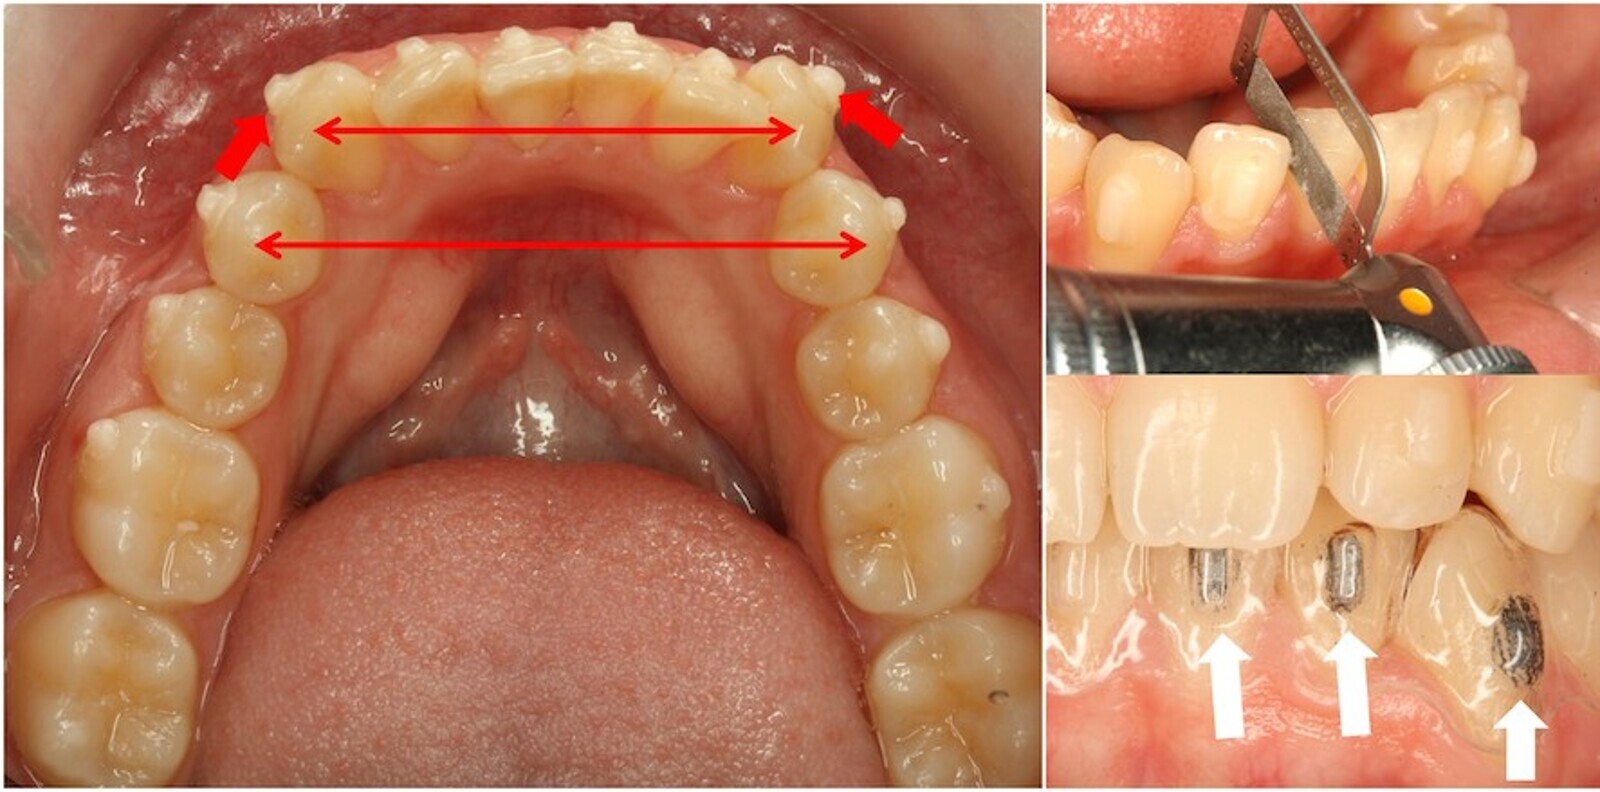

Es necesario siempre recordar la verdad de Perogrullo de los alineadores: para poder mover dientes necesitamos previamente espacio, que podemos conseguir (figura 29) por expansión (flechas rojas finas) o mediante orthostripping mecánico secuencial; para comprobar la adaptación de los alineadores a los ataches podemos pintar estos con lápiz (flechas blancas).

Figura 29. Para mover dientes necesitamos previamente espacio, que podemos conseguir por expansión (flechas rojas finas) o mediante orthostripping mecánico secuencial. Para comprobar la adaptación de los alineadores a los ataches podemos pintar estos con lápiz (flechas blancas).

Caso tratado con alineadores, ataches activos de rotación de cuarto de esfera en caninos y orthostripping de 0,75 mm/diente en la parte anterior de la arcada superior (figura 30).

Figura 30. Caso clínico tratado con alineadores, ataches activos de rotación de cuarto de esfera en caninos y orthostripping de 0,75 mm/diente en la parte anterior de la arcada superior.